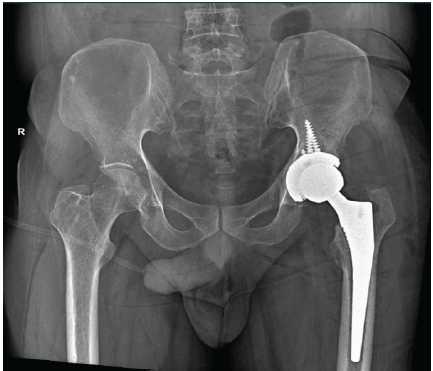

Stage two involved total hip replacement (Fig.4). The post-operative course was uneventful. At 12 months follow-up, the patient reported marked pain relief, improved range of motion, and independent ambulation.

Figure 4: Post-operative radiograph following stage 2 surgery showing well aligned THR.